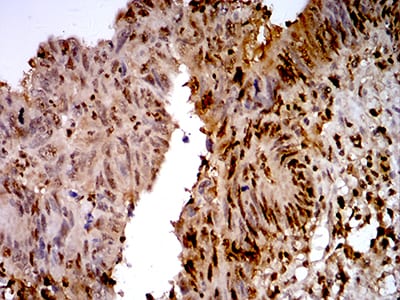

- Immunohistochemical analysis of paraffin-embedded human rectum cancer tissues using TTF1 mouse mAb with DAB staining.